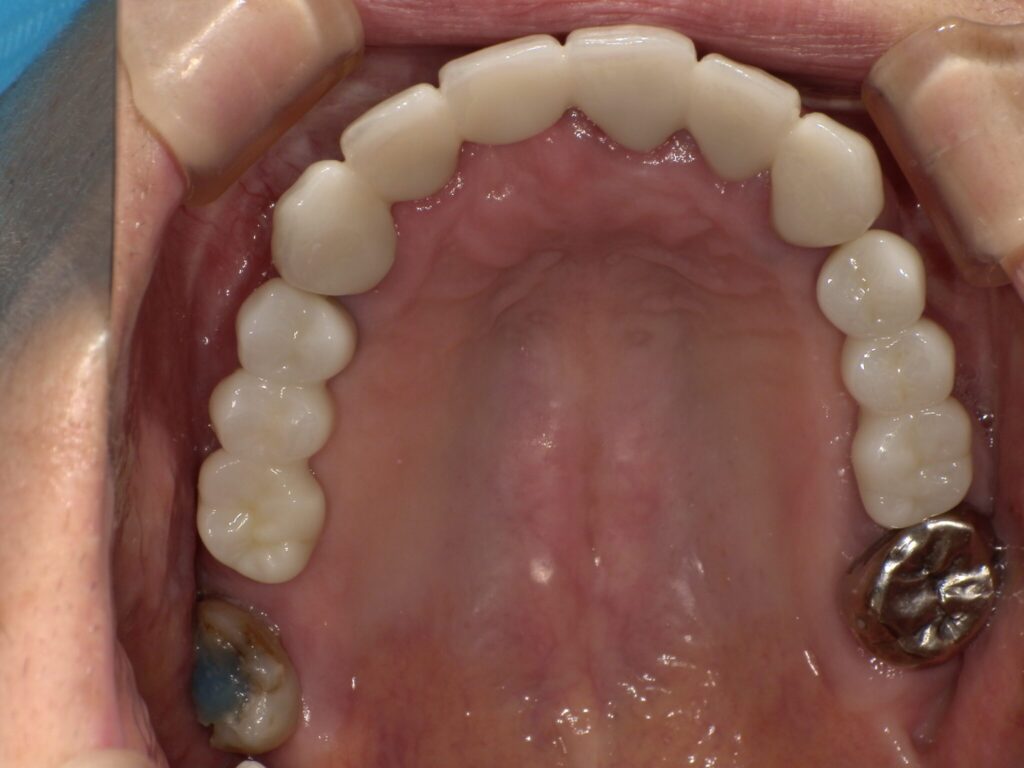

| 治療内容 | インプラント埋入(右上4・6,左上4・6,右下6,左下6) ジルコニアBr(右上3―左上3) ジルコニア(右下5,左下5) |

インプラント 1年5ヶ月/13回 ジルコニアBr、ジルコニアクラウン 3ヶ月/10回 |

| 費用 | インプラント: 2,552,000円 その他治療: 640,000円 合計 3,192,000円 *いずれも税込 |